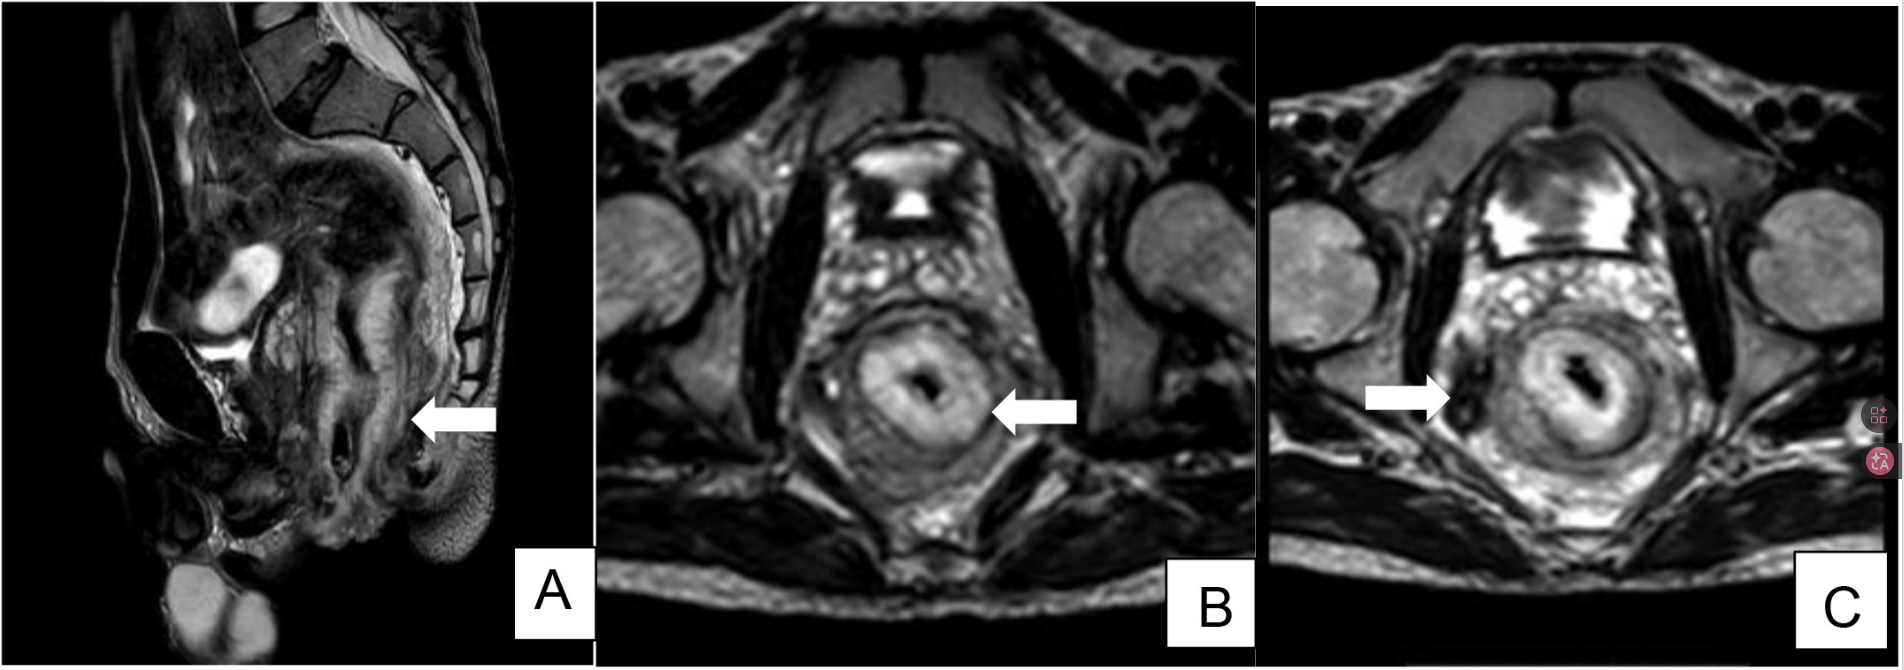

盆腔MRI显示局部侵袭性肛直肠恶性肿瘤,伴弥漫性浸润改变、环周切缘(CRM)阳性及多个直肠系膜淋巴结转移(图1)。分期为T3N2Mx。

图1. (A) 矢状 T2W 图像显示(箭头)不规则环状肿块,类似壁面增厚,涉及肛管和直肠。(B)轴侧 T2W 图像显示弥漫性浸润变化,导致 CRM 阳性;(c) 轴向 T2W 图像显示多个直肠系中膜结节